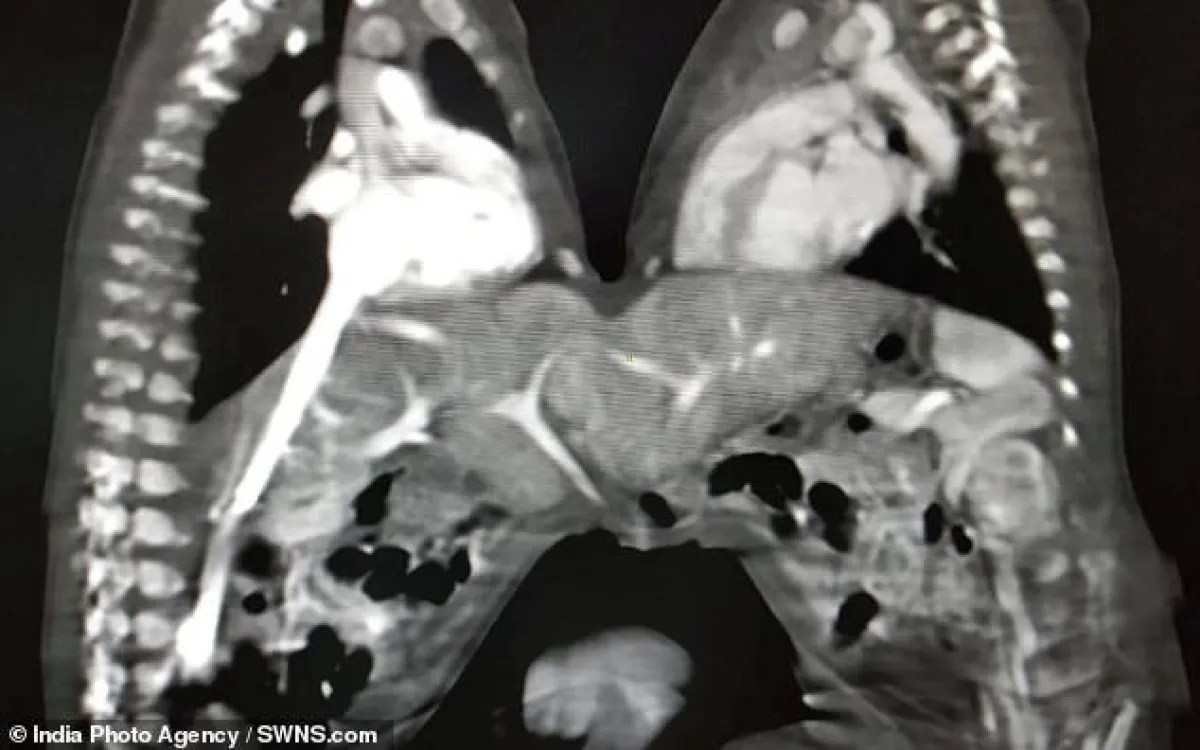

وبحسب موقع "ديلى ميل"، كانت الرضيعتان ملتصقتين من المعدة، ويبلغ عمرهما 3 أيام فى وقت إجراء العملية، ونجح الأطباء فب إقناع أهل التوأم بأن جراحة الانفصال هي الخيار الوحيد لبقائهما أحياء، حيث أثبتت العملية التي استمرت 5 ساعات تحدياً ناجحاً، ومن المتوقع أن يُسمح للفتاتين بالعودة إلى المنزل في وقت لاحق من هذا الأسبوع.

وأجريت العملية في 6 ديسمبر، وقام بها فريق من 5 جراحين و10 أطباء و15 ممرضة، وأخذوا صورة مع الفتاتين اللتين ما زالتا على طاولة العمليات للاحتفال بالعملية التي كانت صعبة بسبب إمدادها بالدم.